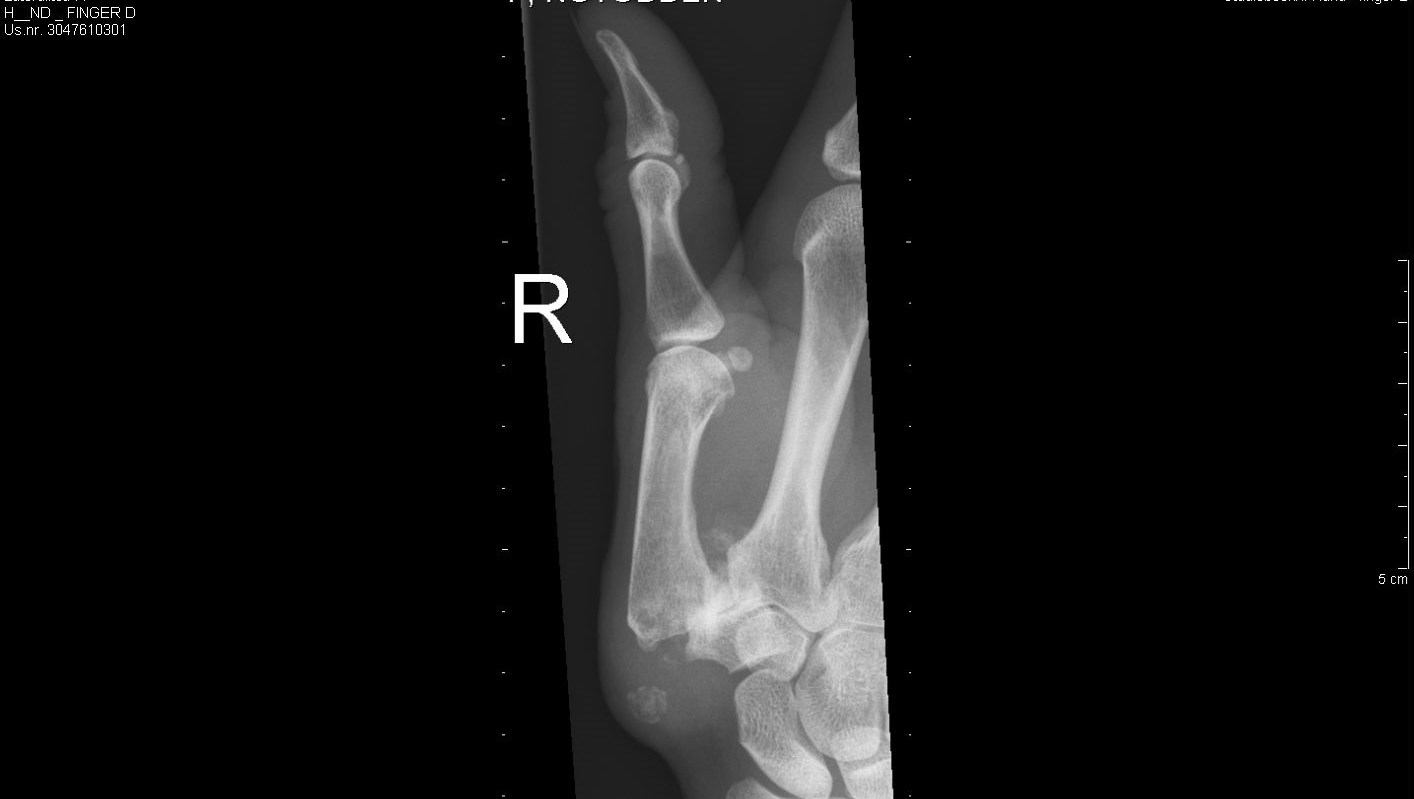

Den vanligaste lokalisationen av primär artros i handen är i tummens carpometacarpalled (CMC 1) – tumbasartros, med eller utan samtidigt engagemang av leden mellan scaphoideum och trapezium (STT-leden).

Tillståndet är 8-10 ggr vanligare hos kvinnor och debuterar vanligen mellan 45-50 år. Kliniskt finner man krepitationer i den engagerade leden samt smärta (”Grinding-test”) vid provokation i form av axial kompression och rotation av tummens bas. Vid engagemang av STT-leden har patienten smärta i handleden vid radialdeviation. Diagnosen fastställs radiologiskt.